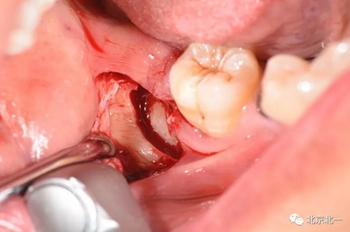

第二步:拔牙

切口設(shè)計(jì)關(guān)鍵點(diǎn)偏頰側(cè)。

去骨:原則暴露最大周徑線即可, 盡可能少去骨, 微創(chuàng)拔除。